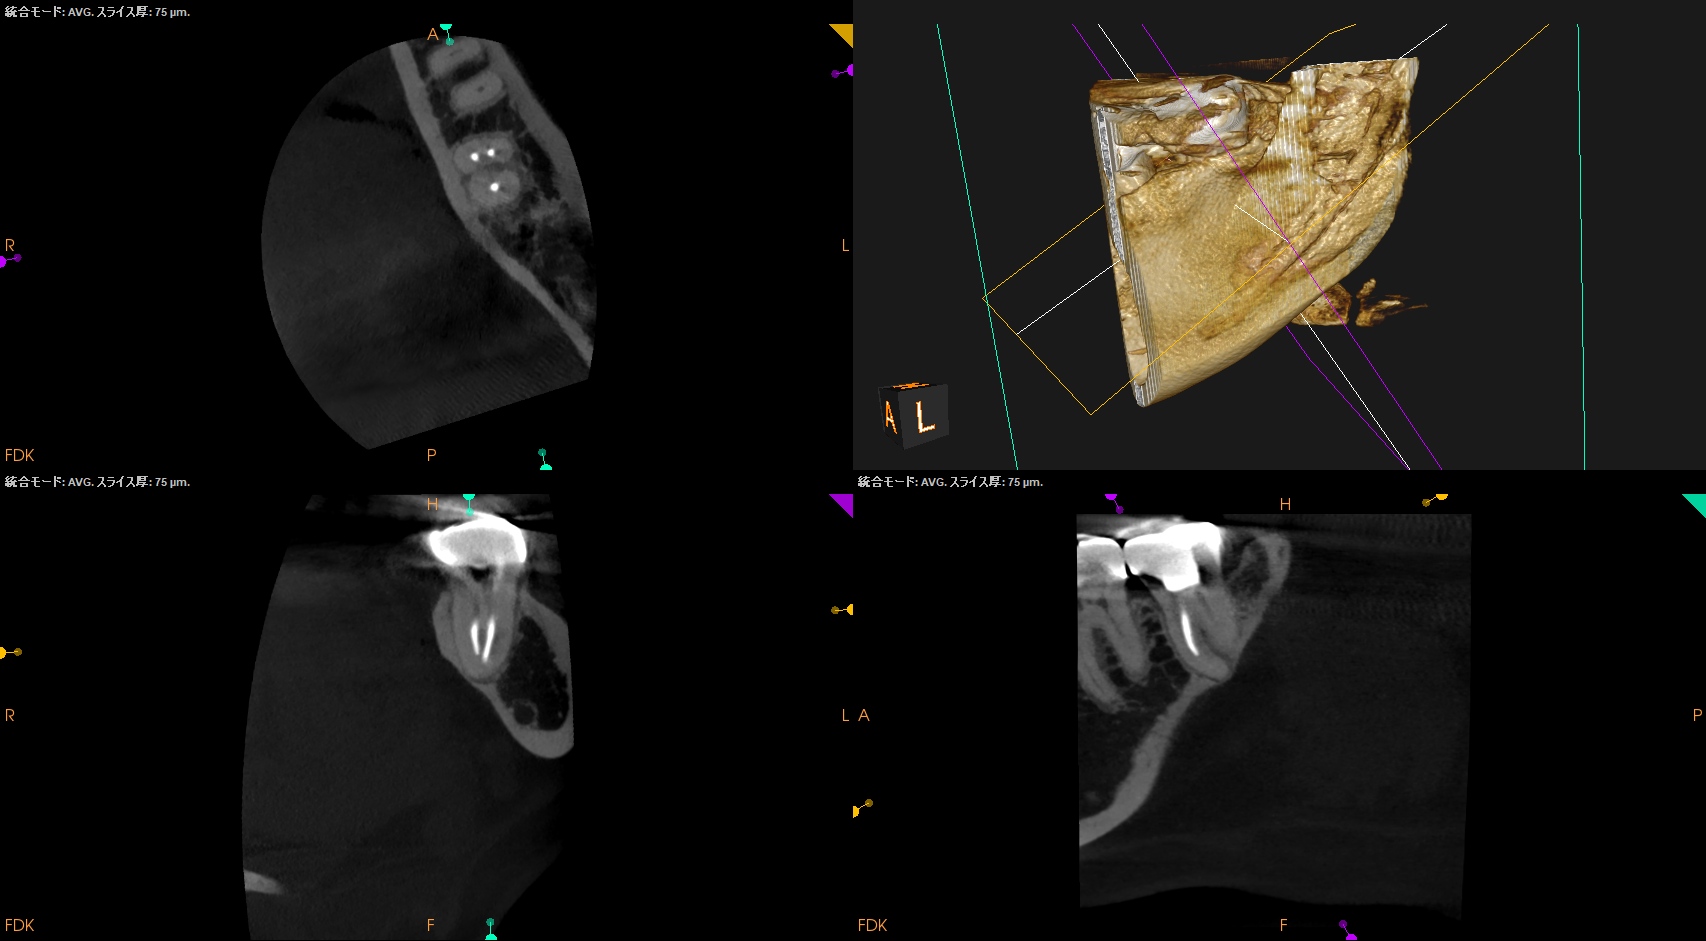

#18 RCT 1yr recall(2026.1.16)

MB

ML

D

1年経過して初診時の臨床症状、根尖病変の発現はないので経過観察も終了とさせていただいた。